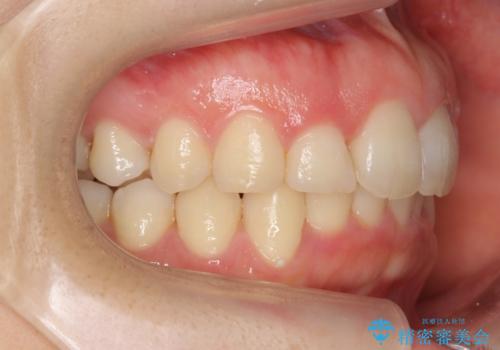

- 前歯のがたがたと出っ歯を主訴に来院。

CTを撮影したところ、臼歯部の頬側の骨の厚みが非常に大きく、通常では考えられない量の歯列の拡大が可能でした。

今回は健康を損なわずに非抜歯で治療が可能でしたが、

歯ぐきや骨の厚みが薄い他の患者さんでは難しいです。

左上5は180度捻転していましたので、そのまま並べています。

遠心移動などは行わず、IPRと拡大のみで治療を行いました。

一般的に非抜歯矯正を無理に行うと、口元がモッコリ出てしまうことがあります。しかし、今回は前歯を前に出さないような設定にしており、口元が出ることもありませんでした。